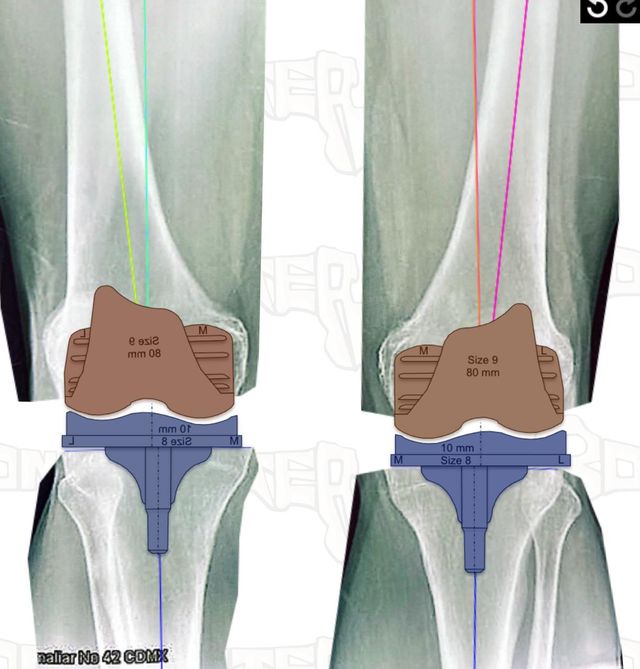

La colocación de una prótesis de rodilla es mucho más que un procedimiento: es el inicio de una nueva etapa de movimiento y calidad de vida. La planeación adecuada es fundamental para asegurar una cirugía precisa y garantizar el mejor resultado para cada paciente.

En mi práctica, cada cirugía se diseña de forma personalizada, evaluando tu anatomía, necesidades y expectativas. Porque una buena planeación no solo define la cirugía, también abre el camino a una recuperación más rápida y una rodilla que te permita volver a disfrutar tus actividades.